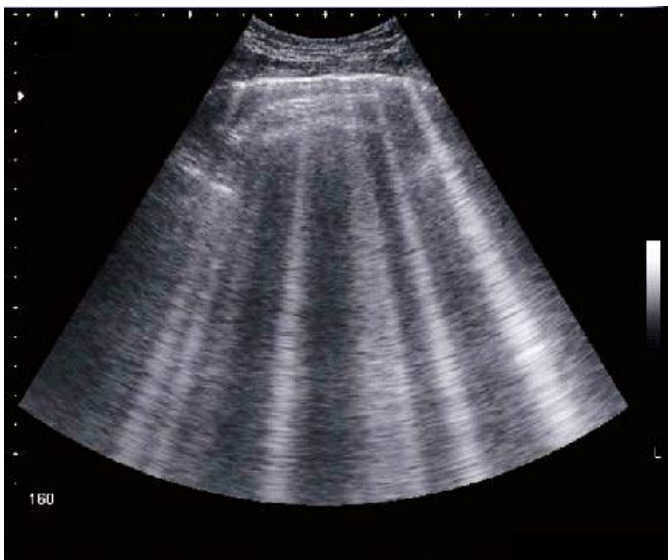

Considerando a imagem de ultrassom abaixo, analise as assertivas a seguir:

I. Esse padrão de imagem pode representar um paciente com doença intersticial pulmonar.

II. Esse padrão é conhecido como padrão A.

III. Esse padrão de imagem transposto para o modo M é visto como o “sinal do código de barras”.

IV. Esse padrão é comum em pacientes com insuficiência cardíaca perfil L.

Quais estão corretas?